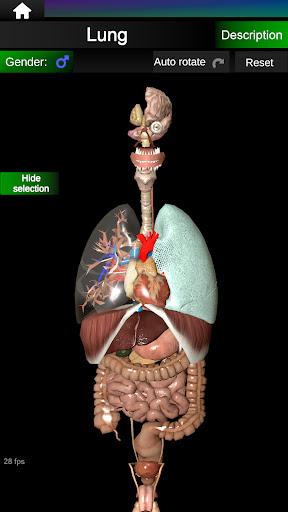

Menampilkan model anatomi 3D dari organ utama tubuh manusia dan penjelasannya masing-masing.

Apa yang ada di aplikasi?

* Sistem pernafasan, yang meliputi trakea, bronkus, paru-paru dan animasi sistem ini.

* Jantung, yang meliputi atrium, ventrikel, aorta, dan animasi organ ini.

* Mudah diakses dan dinavigasi (zoom, rotasi 3D).

* Sembunyikan atau tampilkan informasi.

* Bandingkan organ pria dan wanita.